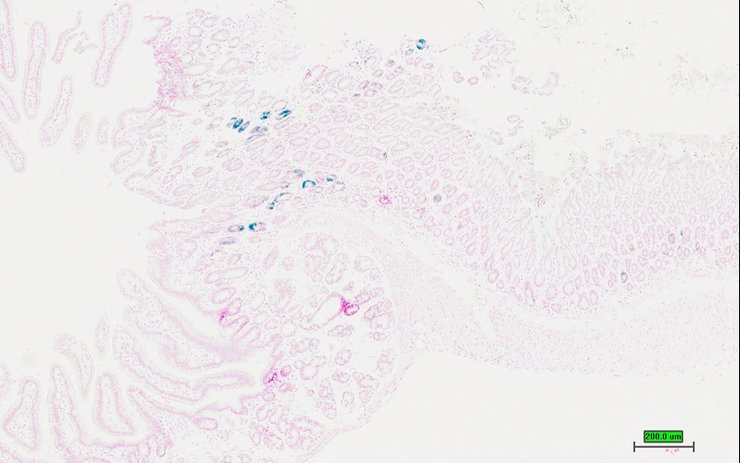

TS28: duodenum Present UC Davis_1883682

Specimen UC Davis_1883683: postnatal adult; Nepntm1b(KOMP)Wtsi/Nepn+ (more )